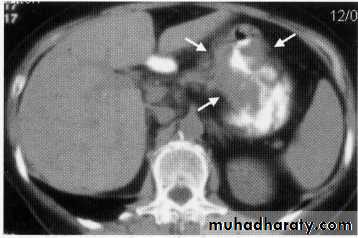

hepatic mets

hepatic mets,arterial phase

hepatic mets venous phase